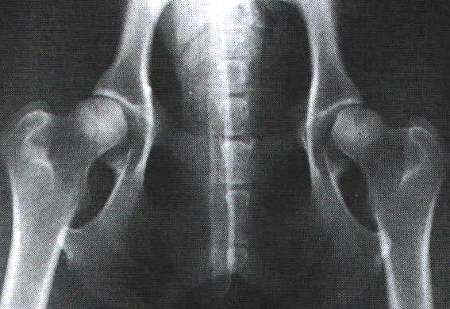

mittlere HD - Aufnahme bei einem Schäferhund |